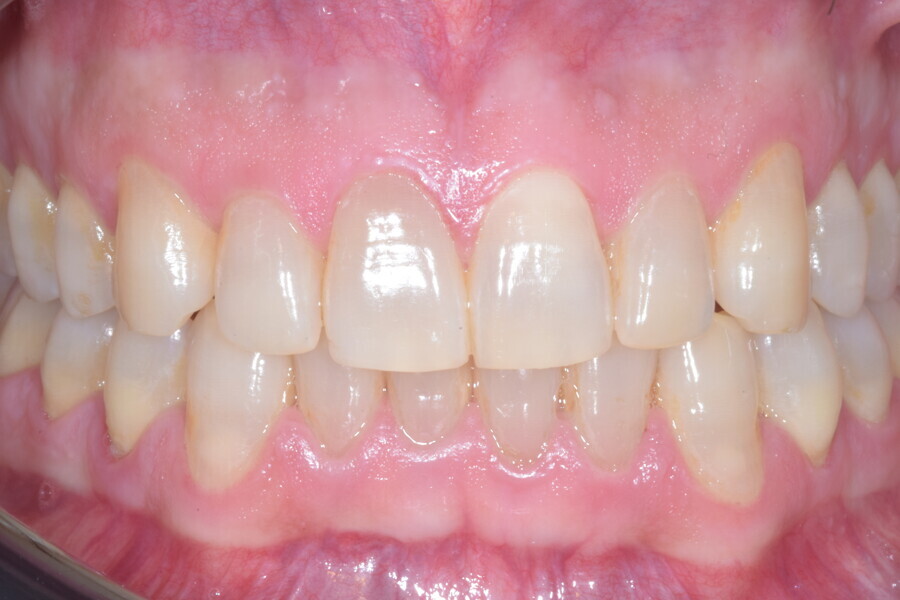

Le plan de traitement numérique (ClinCheck) avait prévu douze aligneurs pour l’arcade maxillaire et dix-sept pour l’arcade mandibulaire. Les objectifs du traitement visaient à combiner les mouvements verticaux d’extrusion des dents postérieures et les mouvements d’intrusion des dents antérieurs, au moyen de rampes d’occlusion, tout en utilisant des taquets d’extrusion pour assurer la désocclusion des dents postérieures et l’intrusion des dents antérieures inférieures, nécessaires au nivellement de l’arcade mandibulaire. La courbe de Spee a été nivelée et le profil plat ainsi que la position des lèvres ont été améliorés par une vestibulo-version des incisives supérieures et inférieures. Le plan avait prévu des élastiques de classe II pour faciliter la vestibulo-version des dents inférieures et les puissants contacts occlusaux postérieurs, avec une extrusion relative des dents postérieures. Une morphologie plus large de l’arcade et une intercuspidation idéale ont été obtenues par des mouvements de torque proches de 0° des dents latérales et postérieures supérieures. Aucune conception technique excessive n’avait été prévue dans le plan de traitement numérique. En raison de l’âge du patient, les aligneurs ont été changés tous les dix jours, dans le cadre d’un traitement d’une durée inférieure à six mois. À la fin de la première série d’aligneurs (Figs. 20–24), un nouveau plan de traitement numérique comportant cinq autres aligneurs a été conçu, en vue d’améliorer l’intercuspidation des molaires sans élastiques. La durée totale du traitement a donc été prolongée jusqu’à 7,5 mois puisque les aligneurs supplémentaires étaient changés toutes les semaines.

À la fin du traitement, on pouvait observer une relation de classe I des canines et des molaires, une légère augmentation de l’inclinaison des incisives supérieures (Ui-FH = 112°), une correction complète de l’inclinaison des incisives inférieures (IMPA = 97,09°) grâce à la vestibulo-version, et une légère amélioration de l’hypodivergence (SN-GoGn = 27°) résultant de l’extrusion relative des dents postérieures, et de l’utilisation d’élastiques de classe II — petite variation (1°) très intéressante compte tenu de l’âge du patient (Figs. 25–35). La ligne du sourire était harmonieuse et correspondait à une relation idéale entre les incisives supérieures et la lèvre inférieure. Le sourire avait été élargi grâce au contrôle du torque des segments latéraux et postérieurs.

Lors du suivi à un an, alors que le patient portait un appareil de rétention (appareil de rétention Vivera avec rampes d’occlusion, Align Technology), le résultat était stable et l’intercuspation était nettement meilleure (Figs. 38–42).